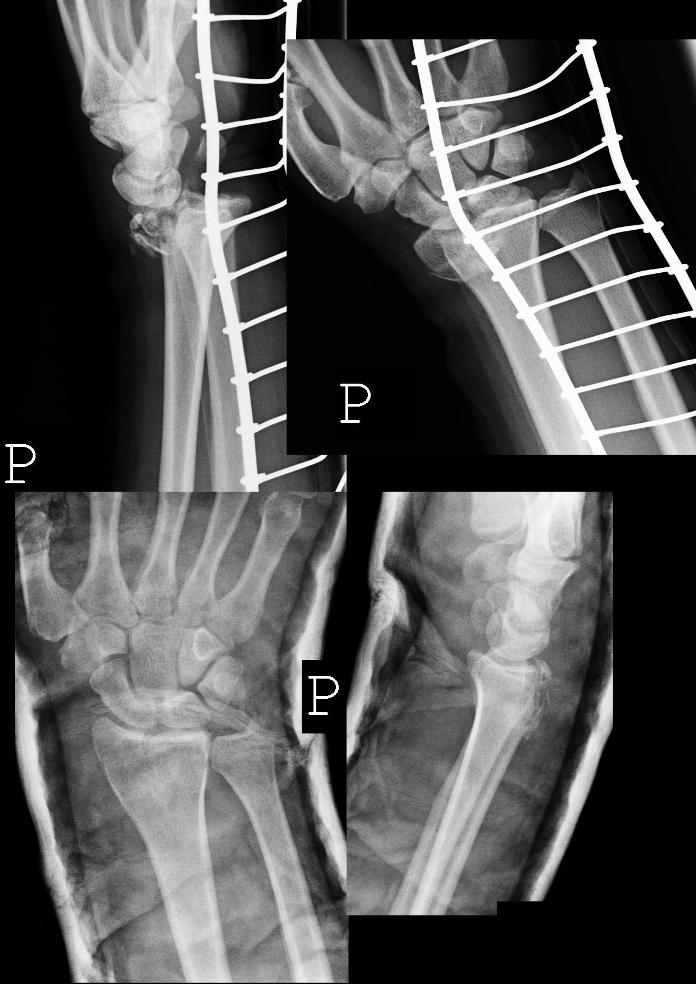

[Ortho] Внутрисуставной перелом дистального метаэпифиза лучевой кости

Уважаемые коллеги, интересует Ваше мнение по следующему клиническому

случаю: Пациент 34 лет, правша, стоматолог. Травма в результате падения

с лошади на выпрямленную конечность два дня назад во Франции, получил

оскольчатый внутрисуставной перелом дистального метаэпифиза лучевой

кости со смещением отломков. Снимки сразу после травмы и после

репозиции. Нейрососудистых нарушений нет. В прошлом - перелом 1 пястной

кости. Каковы будут мнения по возможным методам лечения, ведения и

реабилитации пациента?